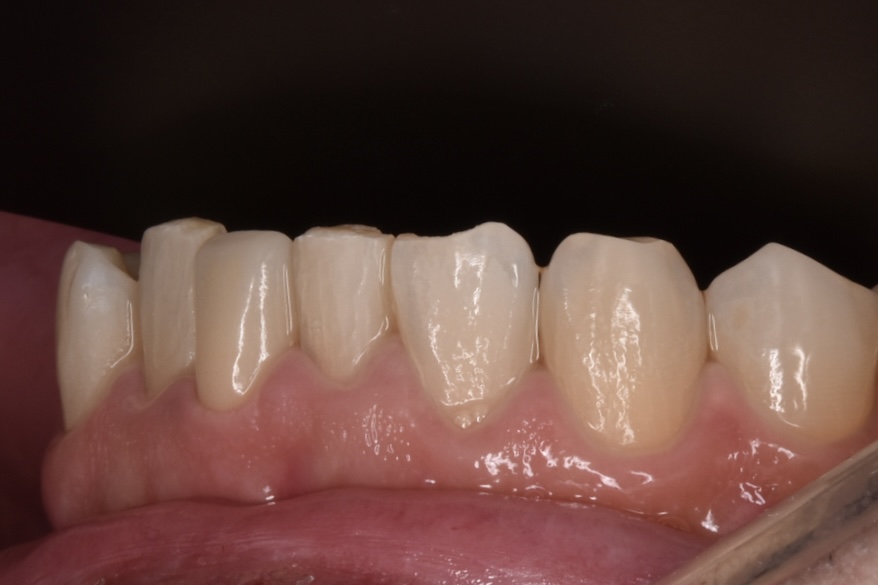

完成したセラミック

さくらジルコニアプランでのジルコニアセラミックです。歯の色はA3というシェードです。色見本が20色近くありますので、そちらから選択して頂きます。